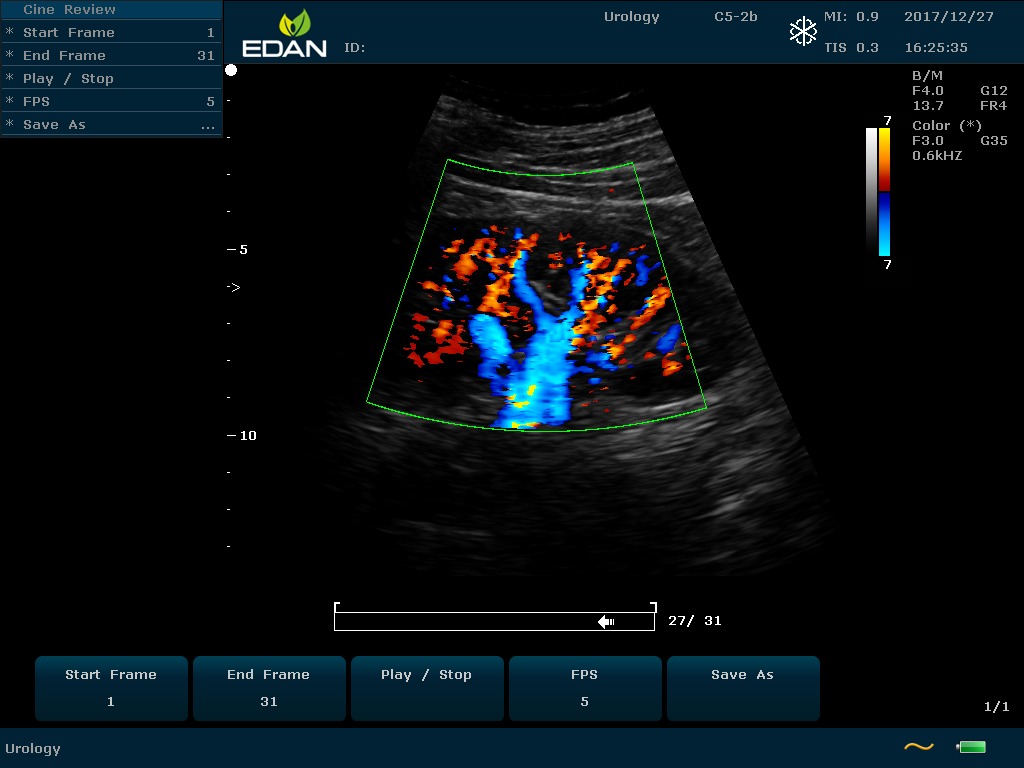

Особенность U60 Edan — расширенное применение. Ультразвуковой аппарат рекомендован для абдоминальных исследований, гинекологии и акушерства, кардиологии, педиатрии, урологии, изучения малых органов, сосудов. Для U60 Edan используются конвексные, линейные, фазированные и внутриполостные датчики.

Передовые технологии позволяют повысить качество визуализации в несколько раз. УЗИ-аппарат U60 Edan отличается возможностью быстрой настройки визуализации. Специальные функции позволяют моментально отображать данные за счет быстрой оптимизации параметров. Режимы визуализации: B-mode, M-mode, Color Doppler, Power Doppler Imaging, Pulsed Wave Doppler, Continuous Doppler.

• Цветовое Допплеровское картирование